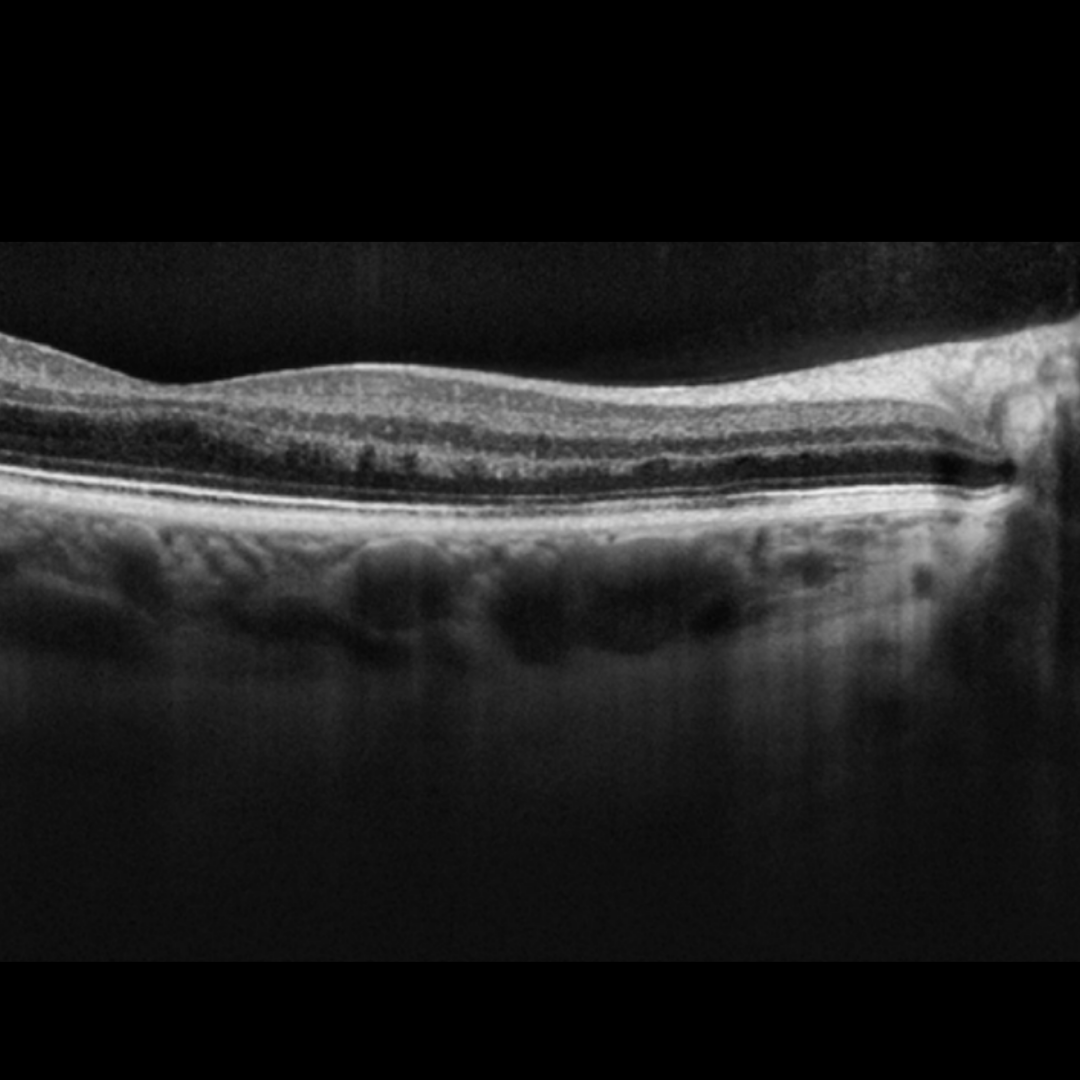

OCT imaging through the lesions usually show disruption of the outer retina.

Cirrus OCT macular line scans (right - top, left - bottom)

Spectralis OCT line scan (left macula)